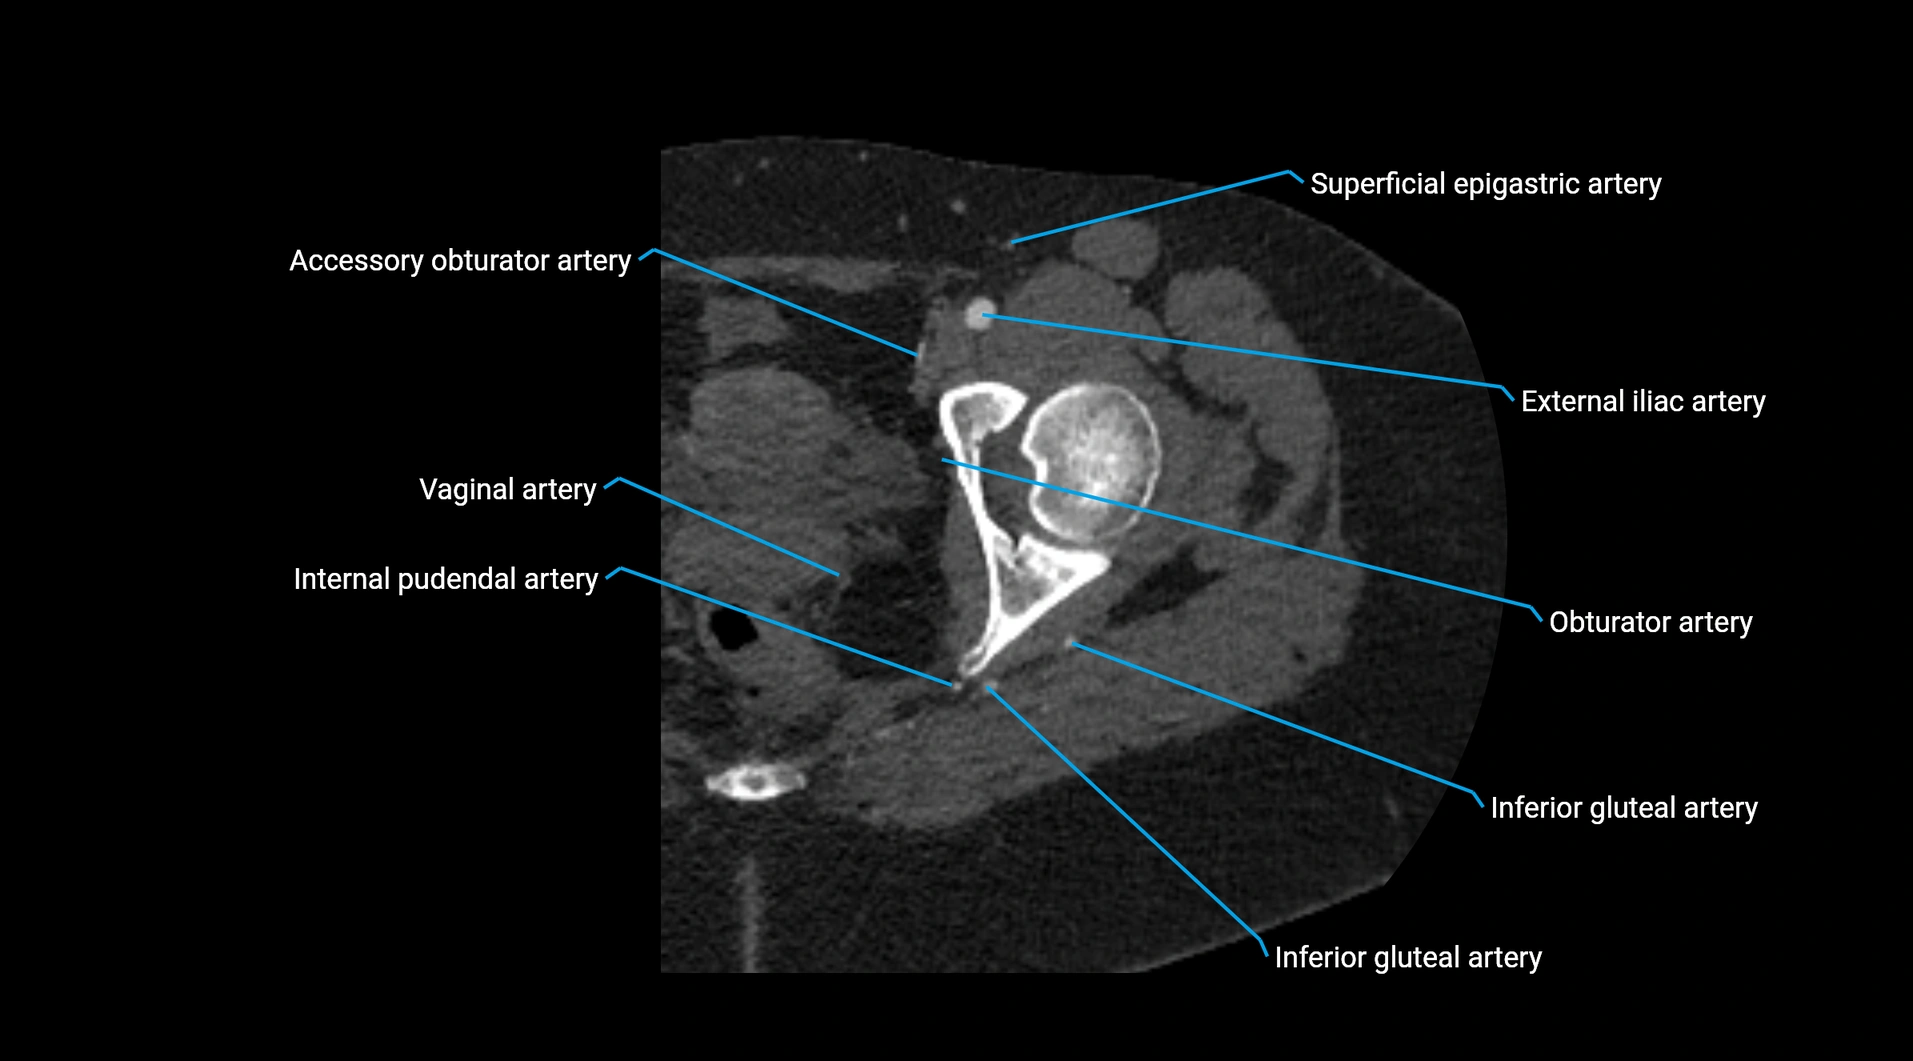

CT images

image